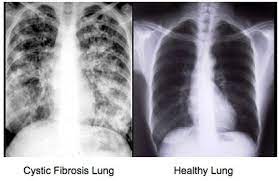

This mucus clogs up the lungs making it hard to breathe and increasing the chances of infection. When genes don’t work properly like this we sometimes call them faulty genes.